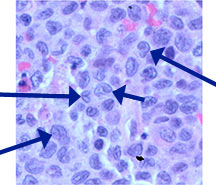

Microscopic Pathology

- Langerhans cell is diagnostic and clonal proliferation

- Nuclei show prominent nuclear groove (coffee-bean)

- Also composed of eosinophils and other inflammatory cells (non diagnostic component)

- Ratio of inflammatory cells to Langerhans cells varies

- Mitotic activity low

- Birbeck Granules: Electron Microscopy demonstrates granules that often take the form of a tennis raquet and form from complex invaginations of the cell membrane

- Vimentin, CD1 and S-100 positivity